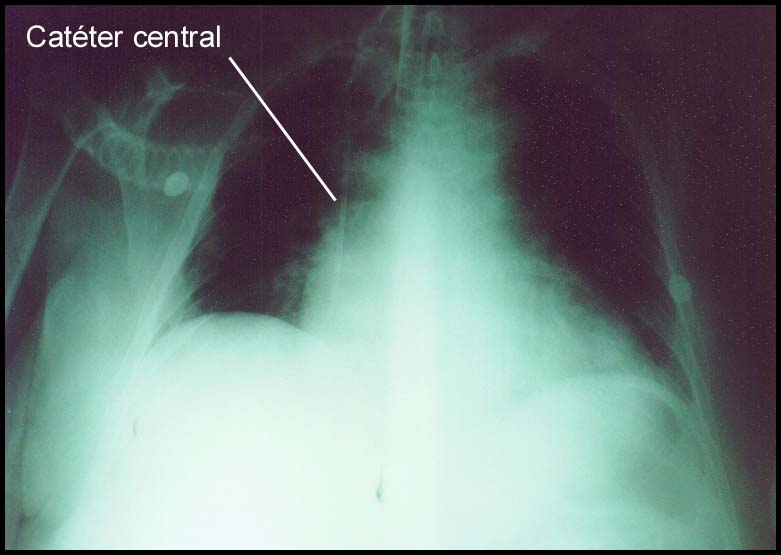

Para a mensuração da PVC, é necessário o

posicionamento de um catéter em veia central (veia cava superior), comumente

utilizando-se de punção percutânea de veia subclávia ou veia jugular interna. É

checado radiológicamente para certificar-se que o catéter esteja bem posicionado e não

esteja dentro do átrio direito.